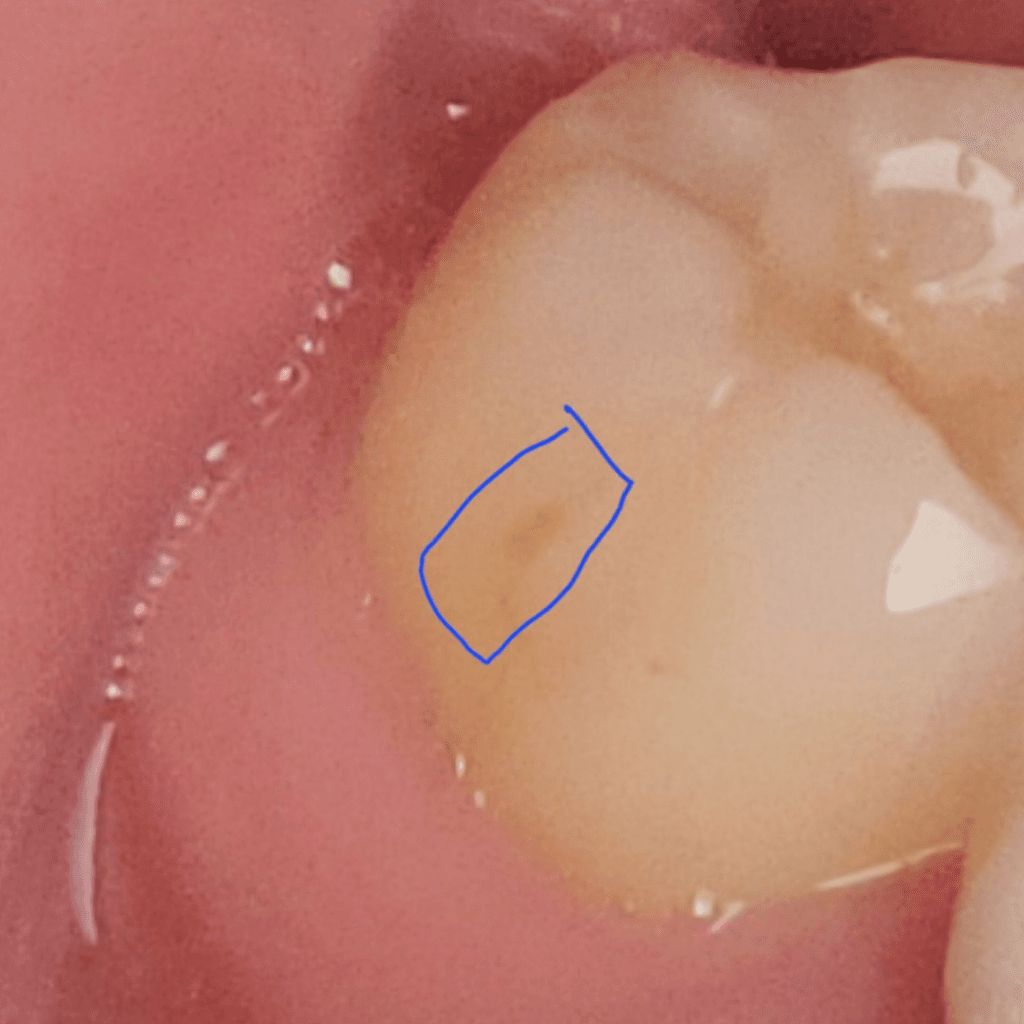

사진만으로는 정확한 답변을 드리기는 어렵습니다. 다만 현재 사진으로 유추해보았을 때는 단순 착색 및 변색일 가능성이 큽니다. 일반적인 충치 양상과는 차이가 있어 보입니다. 물론 정확한 것은 치과 방문 후 검사를 해보셔야 합니다.

충치보다는 착색으로 보입니다. 정확한 것은 치과에 내원하셔서 검진을 받아보셔야 알 수 있습니다.

사진에 보이는건 충치는 아니고 착색이 된거 같습니다. 커피나 흡연을 하게되면 치아 표면에 착색이 발생할수 잇습니다.

현재 사진상으로는 커피로 인한 착색으로 보입니다.하지만 보다 정확한 확인을 위해서는 치과진료가 필요로 됩니다.

레진의 경계부위는 쉽게 착색이 될수 있습니다.

커피를 자주 마신다면 착색이 발생할수 있는데 치과에서 간단하게 제거할수도 있어요.

레진 또는 치아의 착색 및 변색으로 보입니다. 사진상으로는 일단 충치의 소견은 아닌데 증상도 중요합니다. 찬 것이나 단 것에 시린 반응을 해당 치아가 보인다면 충치의 가능성도 있긴 합니다.